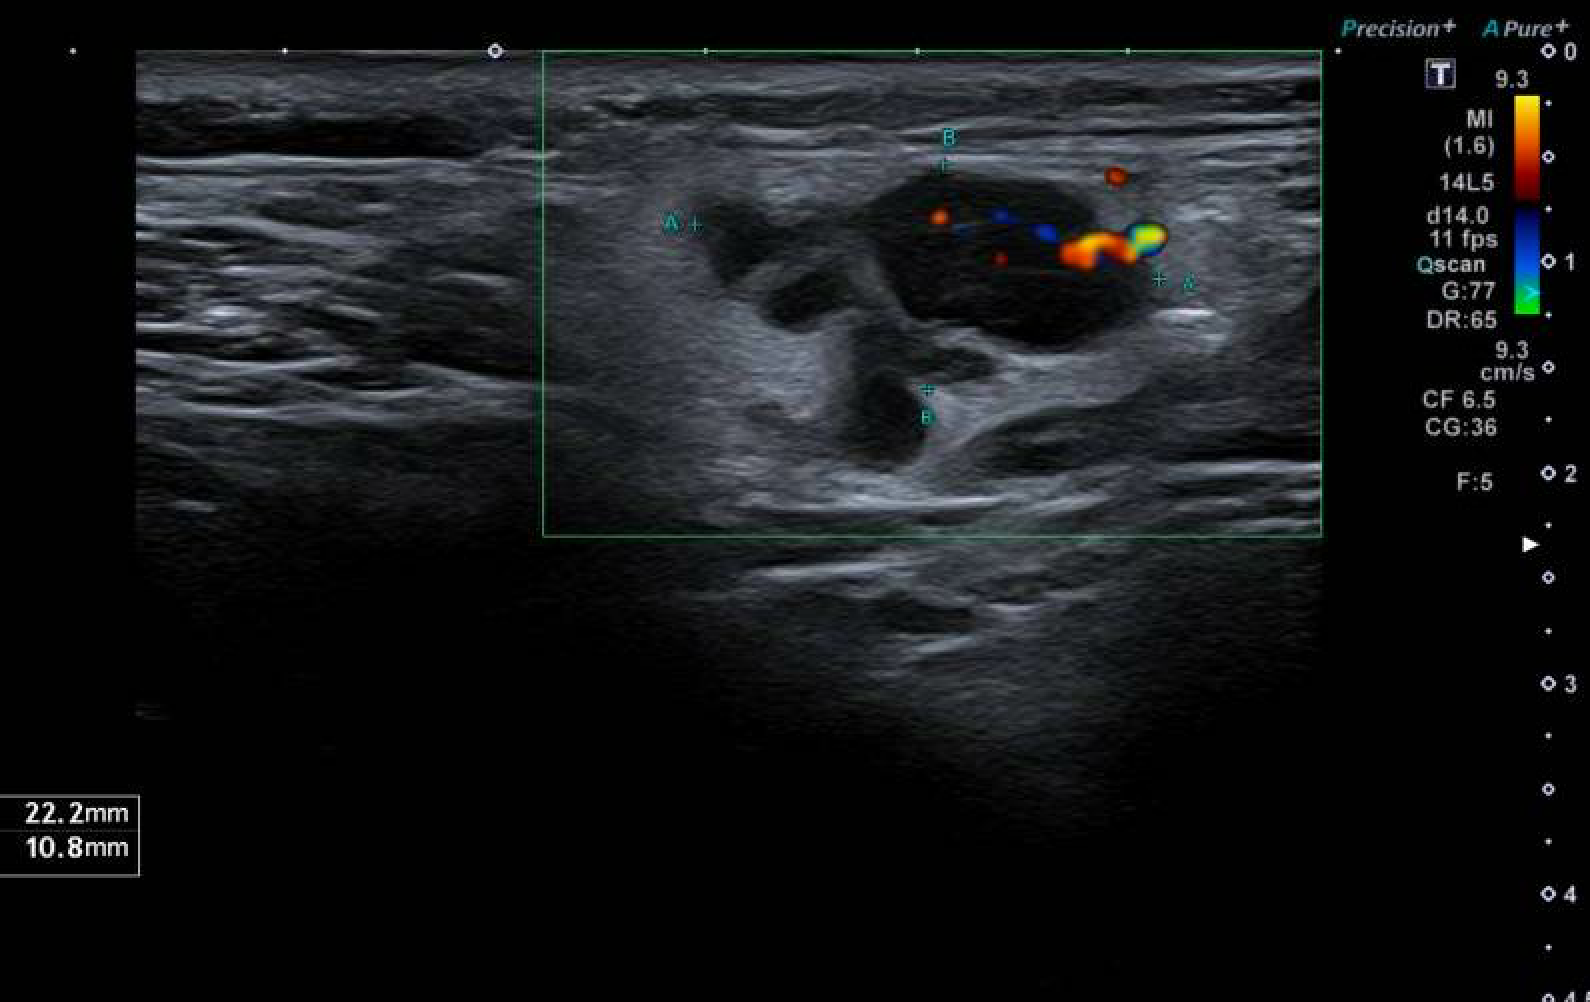

AP: Hombre, 25 años, no RAM, fumador de 10 cigarrillos/día. Antecedente de sífilis tratada. Alergia a ácaros. Convivencia con cuatro gatos. Tratamiento habitual: antihistamínicos a demanda.Hallazgos ecográficos

Se identifica una adenopatía supraclavicular derecha de morfología polilobulada, pérdida del hilio graso, hipervascularización interna y tamaño de 22 × 11 mm, hallazgos claramente patológicos, con pequeños ganglios adyacentes y sin adenopatías laterocervicales significativas.Pruebas complementarias